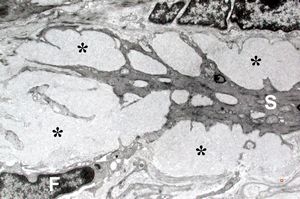

M,60y. | jejunum - amyloidosis

M,60y. | jejunum - amyloidosis(semithin section)